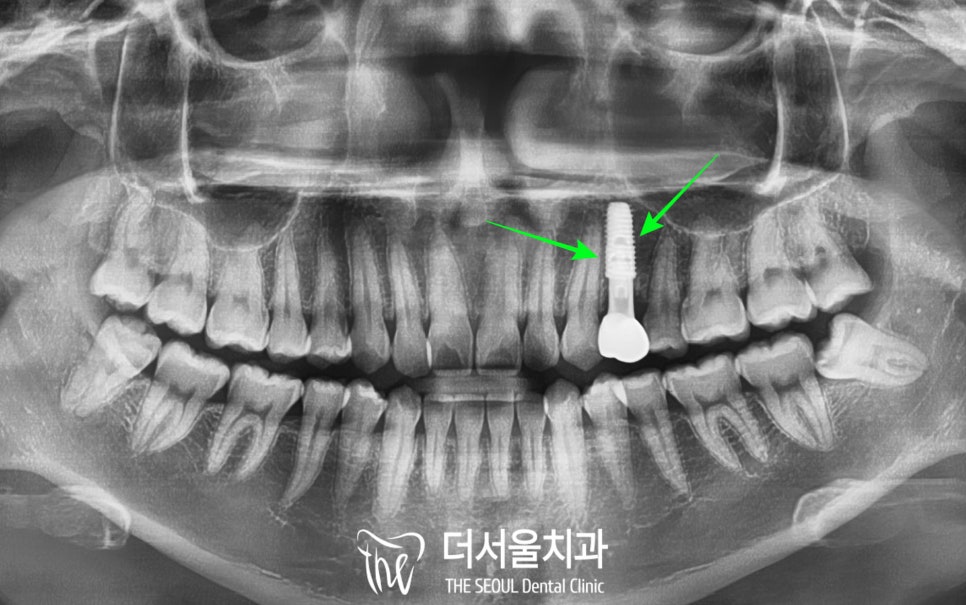

5. 보철 수복

역시 젊으셔서 그런지

회복도 참 빠르셨습니다.

통상 3개월정도는 기다려야

픽스처와 치조골이 단단하게

잘 결합되는데,

이 환자는 2개월반만에

이미 73이라는

안정적인 수치가 나와서

크라운까지 바로 올려드릴 수

있었습니다.

크라운은 지르코니아라는

자연치와 심미성이 유사한

강도 높은 재료를 이용했으며

보철의 교합면에

홀이 있는 SCRP 타입으로

만들었기 때문에

앞으로 사용하시다가

문제가 있거나 불편할때는

홀을 이용하여 유지보수 하실 수 있답니다.